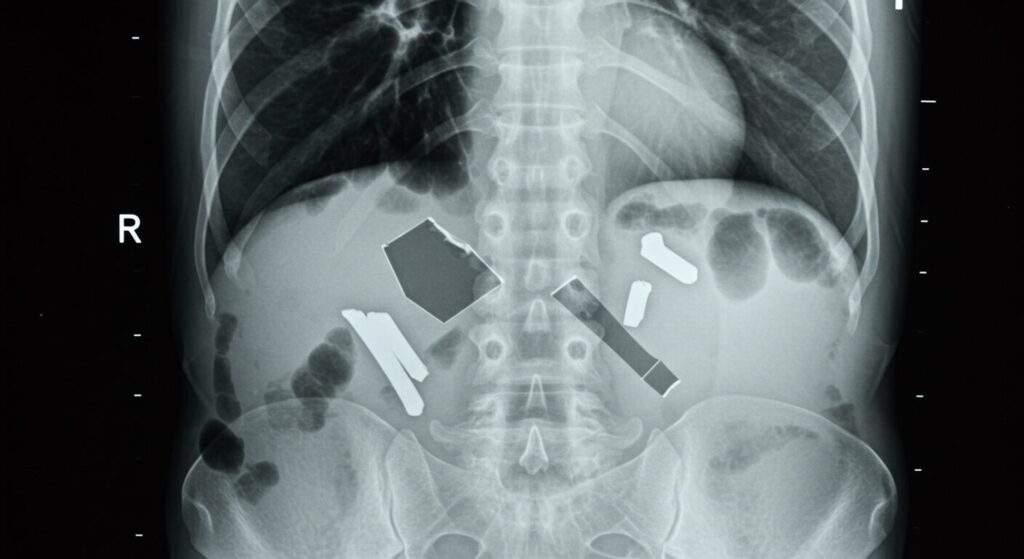

3-1. 金属・プラスチック類:小さなものでも要注意!

レントゲン検査で最も問題になりやすいのが、金属やプラスチック製の部品です 。想像してみてください。X線は金属にぶつかると、まるで壁にぶつかったかのように跳ね返されてしまいます。その結果、画像には非常に明るい白い影が映り込み 、肝心な体の中が全く見えなくなってしまいます。

特に注意してほしいのは、衣類に隠れている「見えない金属」です

• ボタンやファスナー:

シャツやズボンによくありますよね 。

• ブラジャーのワイヤーやホック、アジャスター:

女性は特に気をつけたいポイントです 。

• ラメの糸が織り込まれたTシャツ:

おしゃれなラメにも金属が使われていることがあるんですよ 。

これらは目立たないけれど、診断に必要な領域を完全に覆い隠してしまう可能性があります 。さらに、ネックレス、指輪、時計、ピアスなどのアクセサリー類 、ベルト、ヘアゴムの金属、ヘアピン、眼鏡、入れ歯なども、撮影部位によっては外すよう指示されます。検査室で慌てて外すのは大変ですから、できれば来院前に外しておくのがベストですよ!